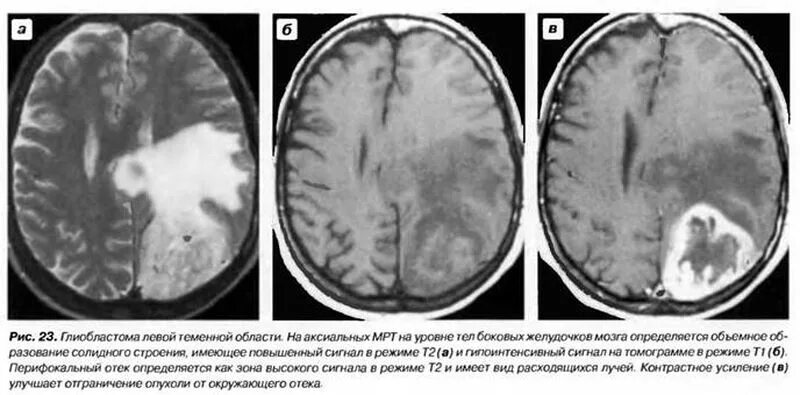

Белые очаги в головном мозге